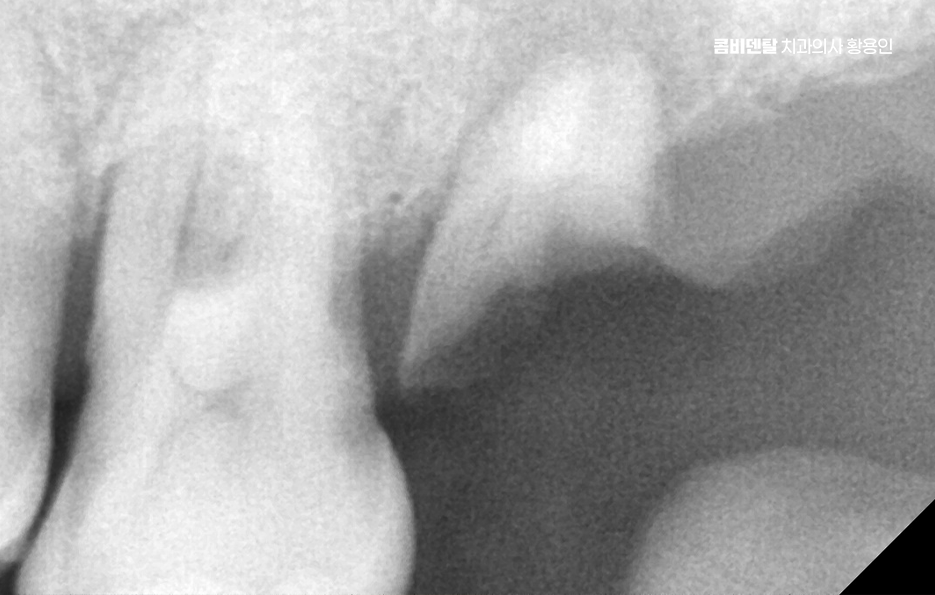

노년기에 자연치아를 잃게 되는 가장 흔한 원인은 치주질환으로 특히 60대 이후부터는 장기간 관리되지 않은 치주염이 진행돼서 결국 치아가 흔들리거나 빠지게 되는 경우가 많으며 일부는 오래된 보철물이나 충치가 원인이 되기도 하는데 자연치아가 하나 빠지면 단순히 그 부위만의 문제가 아니며 주변 치아들이 그 공간으로 쓰러지거나 이동하게 되고, 전체 치열이 무너지기 시작하는 거예요

그러면 한두 개의 상실이 전체 구강 구조를 무너지게 만들고, 결국은 씹는 힘도 약해지며 고령일수록 이런 변화가 더 빠르게 진행되기 때문에, 빠른 대응이 중요할 수 있었어요

그 뿐 아니라 예를 들어, 잇몸뼈가 너무 많이 녹아 있는 경우에는 뼈이식이나 상악동 거상술 같은 부가적인 치료가 필요한 경우도 많기 때문에 경험 많은 의료진과 치료 과정을 함께하는 것이 중요하며 장기적으로도 오래 함께할 치과를 잘 판단하실 필요가 있어요